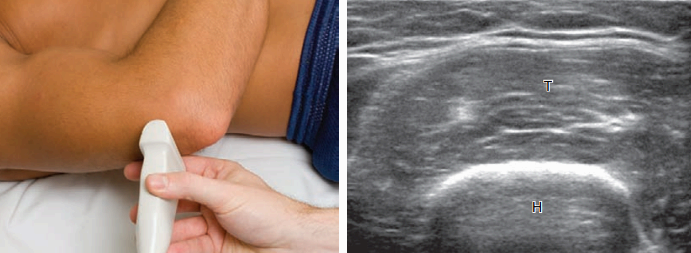

반응형팔꿈치 초음파검사는 환자가 앉은 자세에서 팔꿈치를 검사대에 올려놓고 시행하게 되며, 때로는 누운 자세에서 검사할 수 있다. 대부분의 구조물들이 표층에 있으므로 적어도 10 Mhz 이상의 고주파수 탐촉자를 사용한다. 증상이 있거나, 환자의 병력을 고려하여 해당 부위를 중점적으로 검사한다. 팔꿈치의 모든 부위에 대해 검사를 실시해야 하며, 검사자는 정상 해부 및 정상 변형(normal variant)에 익숙해야 하고, 빠르고 효과적인 초음파 테크닉을 익혀야 한다.

뒤쪽검사(posterior) 팔꿈치의 뒤쪽 구조물을 검사하려면 환자의 팔꿈치를 굽혀야 한다. 누운 자세에서 환자의 손을 배 위에 가로 방향으로 놓는다. 검사할 중요 구조물들은 뒤쪽관절오목, 위팔세갈래근, 팔꿈치머리 부위의 연조직(soft tissue)이다.